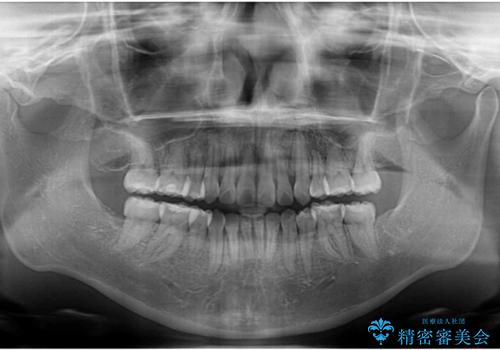

- 治療期間

- 1年7ヶ月

気になっていた八重歯は装置装着から3か月ほどで解消されました。

2年以内を目標として治療を開始しましたが、1年半ほどで終えることができました。